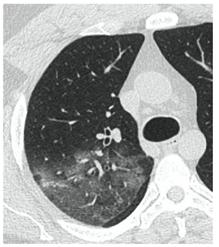

КТ имеет высокую чувствительность в выявлении изменений в легких, характерных для COVID-19. Применение КТ целесообразно для первичной оценки состояния ОГК у пациентов с тяжелыми прогрессирующими формами заболевания, а также для дифференциальной диагностики выявленных изменений и оценки динамики процесса. КТ позволяет выявить характерные изменения в легких у пациентов с COVID-19 еще до появления положительных лабораторных тестов на инфекцию с помощью МАНК. В то же время, КТ выявляет изменения легких у значительного числа пациентов с бессимптомной и легкой формами заболевания, которым не требуется госпитализация. Результаты КТ в этих случаях не влияют на тактику лечения и прогноз заболевания при наличии лабораторного подтверждения COVID-19. Поэтому массовое применение КТ для скрининга асимптомных и легких форм болезни не рекомендуется.

В связи с этим КТ может быть исследованием "первой линии" в тех медицинских организациях/территориях, в которых имеется достаточное количество аппаратов и кадровое обеспечение для выполнения требуемого объема исследований без ущерба для своевременной диагностики других болезней (онкологических, неврологических и т.д.) у наиболее нуждающихся в этом исследовании пациентов.

4. Все выявляемые при лучевых исследованиях признаки, включая КТ-симптомы, не являются специфичными для какого-либо вида инфекции и не позволяют установить этиологический диагноз. Вне клинической (эпидемической) ситуации они не позволяют отнести выявленные изменения к пневмонии COVID-19 и дифференцировать их с другими пневмониями и невоспалительными заболеваниями. Данные лучевого исследования не заменяют результаты обследования на РНК SARS-CoV-2. Отсутствие изменений при КТ не исключают наличие COVID-19 и возможность развития пневмонии после проведения исследования.